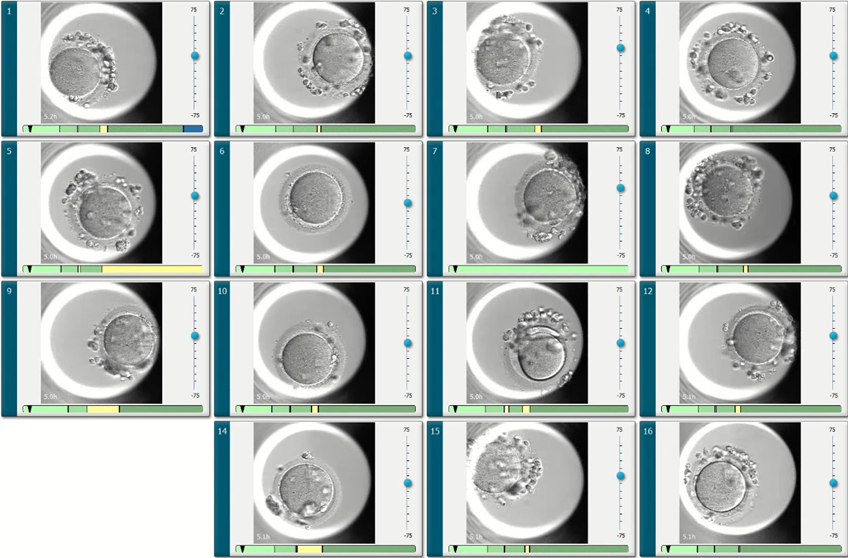

培養箱內建高解析度的攝影機和顯微鏡,可針對每一個胚胎,每10分鐘拍攝一次生長發育影像(也就是縮時攝影技術)。相較於傳統培養箱(一天只能觀察一次到兩次),縮時攝影培養箱可以對每一個胚胎每天照144張相片,也就是觀察144次。經由連續放映,每一顆胚胎都能拍出培養期間的動態影像,胚胎技術師可透過電腦軟體更仔細的觀察胚胎動態的生長發育狀況。並用內建的電腦軟體演算法,來挑選最佳的胚胎進行植入或冷凍。

相較於傳統胚胎培養箱,只能觀察胚胎靜態生長狀況,縮時攝影胚胎培養箱的選胚準確度優於傳統培養箱。最重要的是無須將胚胎從培養箱取出,就可完成上述工作,胚胎也能維持在 恆溫、恆濕、酸鹼度恆定,完全不受干擾的最佳環境下生長